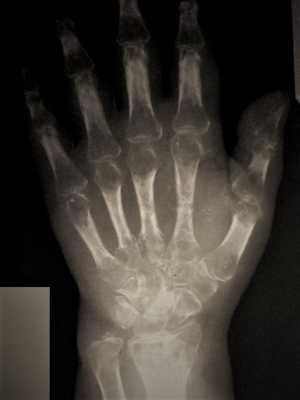

Стадия Зудек I (острая). Характеризуется отсутствием клинических симптомов улучшения (уменьшение боли, гиперемии кожи, уменьшением припухлости, сморщивания кожи т.д.), которые в нормальных условиях появляются уже в конце первой недели после повреждения. Отёк не только не уменьшается, но даже увеличивается, кожа гиперемирована, боли усиливаются, присоединяются неукротимые, не котирующиеся препаратами из группы НПВС - ночные боли. Пациент не может уснуть, как следствие истощение нервной системы на фоне прогрессирующей бессонницы. Боли не уменьшаются ни при иммобилизации (гипсовая, с использованием ортеза при растяжениях и ушибах), ни при поднятом положении конечности. Прикосновение к этому отделу конечности, особенно надавливании на мышцы, вызывает нестерпимую боль. К концу второй недели красный цвет кожи может переходить в синюшный, отмечается атрофия мускулатуры (пальцы «не слушаются, не сгибаются - сильная боль и .т.п.). Активные движения в суставах кисти резко ограничены, болезненны. На четвертой недели рентгенограмма костей кисти с захватом лучезапястного сустава показывает неравномерное затенение (на рентгене как просветление). Если имеется рентгенограмма обеих кистей и предплечья, то признаки остеопороза наиболее рано выявляются в дистальных эпифизах пястный костей.

Стадия Зудек II (дистрофия). Боли в кисти держатся и не проходят. Суставы неподвижны, попытки пассивного (самостоятельно здоровой рукой двигать пальцы больной кисти) движения вызывают резкое усиление постоянно нестерпимой боли. Кожа цианотичная, на ощупь холодная, часто отмечается сильное потоотделение (ладонь больной кисти мокрая от пота). На рентгенограмме неравномерное затенение выражено не так ясно, как в 1-й стадии. Рисунок принимает облачный характер, балочки губчатой кости исчезают, корковый слой суживается. Контуры кости выявляются так ясно, как будто бы они очернены карандашом.

Стадия Зудек III (атрофия). В отдельных, далеко запущенных случаях и при крайне позднем обращении за квалифицированным этиотропным лечением, несмотря на предпринятые меры, патологический процесс не улучшается и в течение полутора-двух лет, от момента заболевания или травмы, доходит до конечной стадии. Кисть атрофична, холодная, суставы неподвижны. Ногти четко показывают трофические расстройства. Боли полностью прекращаются. Дифференцированные скользящие ткани кисти замещаются соединительной тканью (кисть как в панцире-перчатке, кожа в складки на тыле при защипывании не собирается). В этой стадии на рентгенограмме выявляется бедность костей известью, и помимо этого хорошо видны балки губчатой кости (крайне выраженная картина «тигрового» остеопороза).